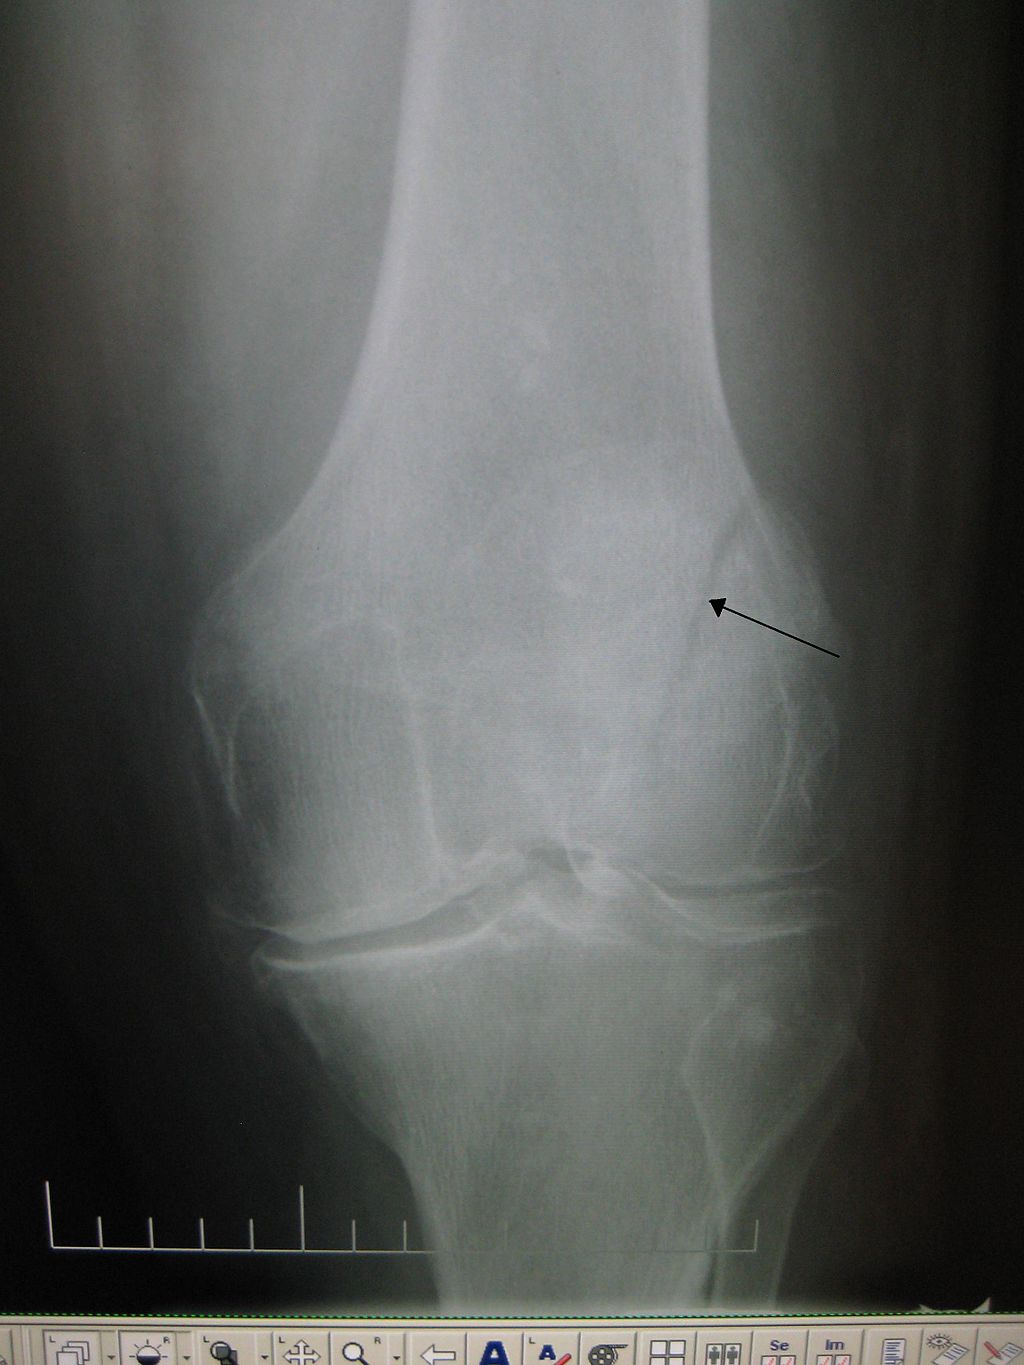

Broken Knee X-Ray . A patella fracture is a break in your kneecap — the small, flat bone that covers and protects your knee joint like a shield. It’s usually caused by direct. Patella fractures are traumatic knee injuries caused by direct trauma or rapid contracture of the quadriceps with a flexed knee that can lead to loss of the extensor mechanism. Symptoms of a knee fracture include pain, swelling, and bruising at the site of injury; And difficulty bearing weight to walk or stand. The doctor may put mild pressure on the kneecap, and may bend or straighten the leg to see if those actions cause or increase pain or reveal a deformity. Treatment for a fractured kneecap

Xray images showing real fracture of broken leg bone under the knee Broken Knee X-Ray The doctor may put mild pressure on the kneecap, and may bend or straighten the leg to see if those actions cause or increase pain or reveal a deformity. Symptoms of a knee fracture include pain, swelling, and bruising at the site of injury; Patella fractures are traumatic knee injuries caused by direct trauma or rapid contracture of the quadriceps. Broken Knee X-Ray.